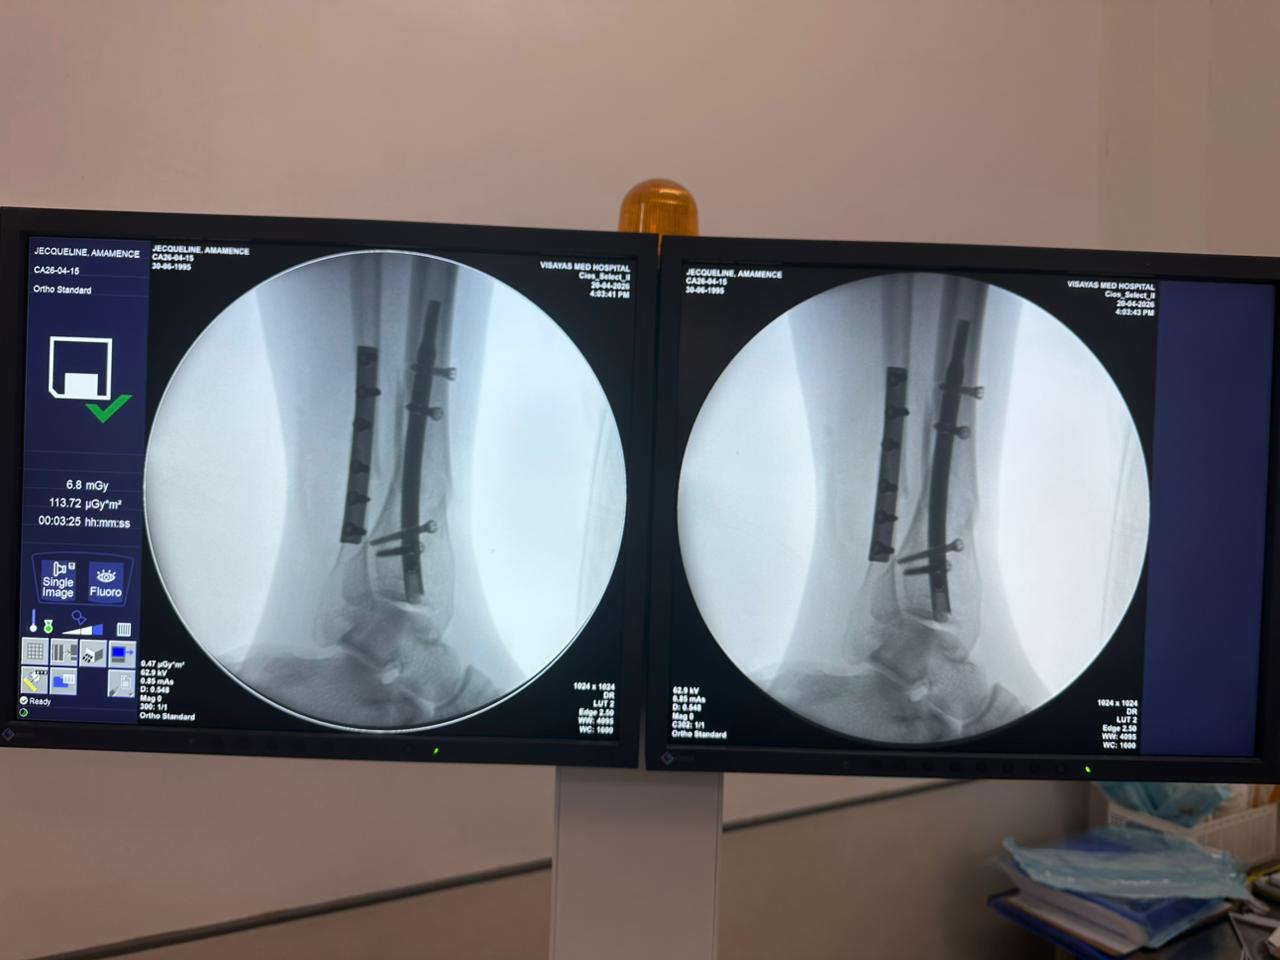

Distal Tibial Kuku Fiksasi Case Study kalawan Fibular Plate Rojongan

Kasus ieu ngalibatkeun fiksasi tibial distal nganggo paku tibial distal intramedullary. Fluoroskopi intraoperatif dikonfirmasi posisi paku, sekrup konci distal, sareng fibular plate fibular.

distal-tibia-fibula-fiksasi-kasus-CZMEDITECH

distal-tibial-nail-case-31-year-old-patient-ap-view-czmeditech